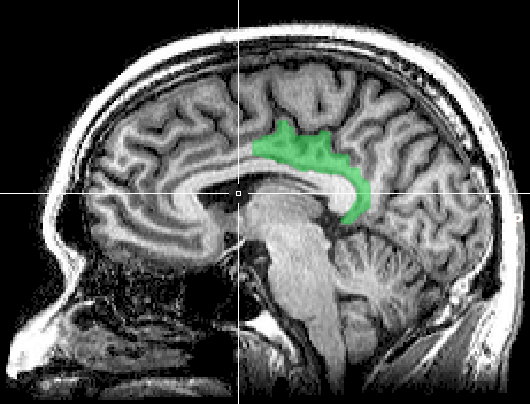

研究者たちが注目したのは、脳の中で記憶や連合に深く関わる後部帯状皮質(posterior cingulate cortex, PCC)です。

この部位はアルツハイマー病患者では萎縮が見られることが知られており、その保護や活性化が認知症予防の観点から重要とされています。

MRIの結果、バラの香りを継続的に身につけていた参加者は、対照群に比べて灰白質の体積が増加していることが確認されました。

ただし、その変化は脳全体に一様に現れたわけではなく、部位によって差が見られました。

Continuous inhalation of essential oil increases gray matter volumeより ・扁桃体(amygdala):香りや感情の処理に関与する領域だが、ここでは大きな変化は観察されなかった

・眼窩前頭皮質(orbitofrontal cortex):快い香りを処理する領域がら、ここでも顕著な変化は見られなかった

・後部帯状皮質(posterior cingulate cortex, PCC):記憶や連合に関わる領域で、顕著に灰白質の体積が増加していることが確認された

この結果は、脳が香りに対して特定の適応を行っていることを示唆しています。